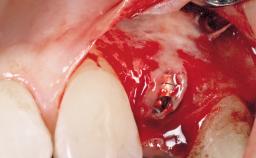

A 33-year-old female patient presented with an upper left central incisor that required extraction after a failed endodontic therapy. The tooth had been traumatized when the patient was a teenager and had undergone several endodontic treatments, including two apicectomy procedures. The patient was in good health and did not smoke. Clinical examination showed that the patient had a high lip line. In full smile, the gingival margins of the upper teeth were visible to the first molars. The gingival margins of central incisors 11 and 21 were only just showing. Examination of tooth 21 confirmed that the tooth was mobile and had hypererupted by 1 mm.

Placement Protocol Immediate implant placement

Socket Integrity Damage to one or more bone walls

Bone Volume Damage to one or more socket walls